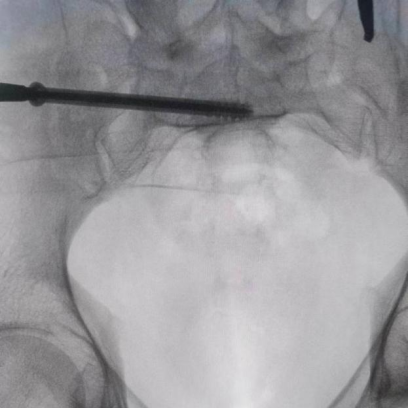

圖為機(jī)器人完成患者信息二維圖像采集后設(shè)計出螺釘置入方向

圖為透視下見置入的骶髂螺釘,位置、長度精準(zhǔn),無絲毫偏差